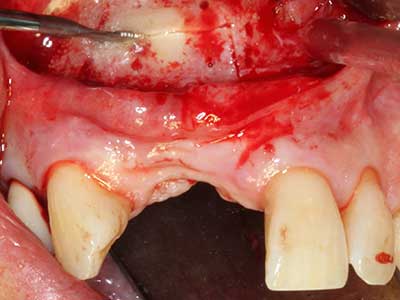

Indication: Periodontal therapy

Marginal periodontal diseases are the main reason for extractions in advanced age. These diseases are primarily caused by bacterial colonization of the gingival pocket, which causes inflammation followed by loss of the periodontium. The formation of subgingival biofilms and concrements is a significant aetiological factor for marginal bone atrophy, so their removal is an important part of the treatment (Drisko 2014, Plessas 2014).

Initial and surgical treatment phases are differentiated in the treatment of marginal periodontitis. In addition to instruction in oral hygiene and motivating patients, both phases should include adequate cleaning of the root surface. In the regenerative setting an open access is generally preferred. The root surface can be cleaned by piezosurgery using special attachments, where instruments with different curvatures are used to reach areas that are difficult to access, such as furcations. The integrated irrigation in the system flushes the detached concrements and bacteria out of the pocket. Specialized systems such as the Piezomed also include application feedback to minimize the ablation of hard dental substance. The greater the pressure on the periodontal attachment the greater the reduction in the amount of ablation.